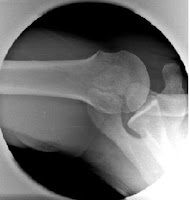

肩峰小骨在X光,尤其是肩的腋窩投射照(Axillar View),可見到肩峰小骨關節,診斷不難(圖3)。